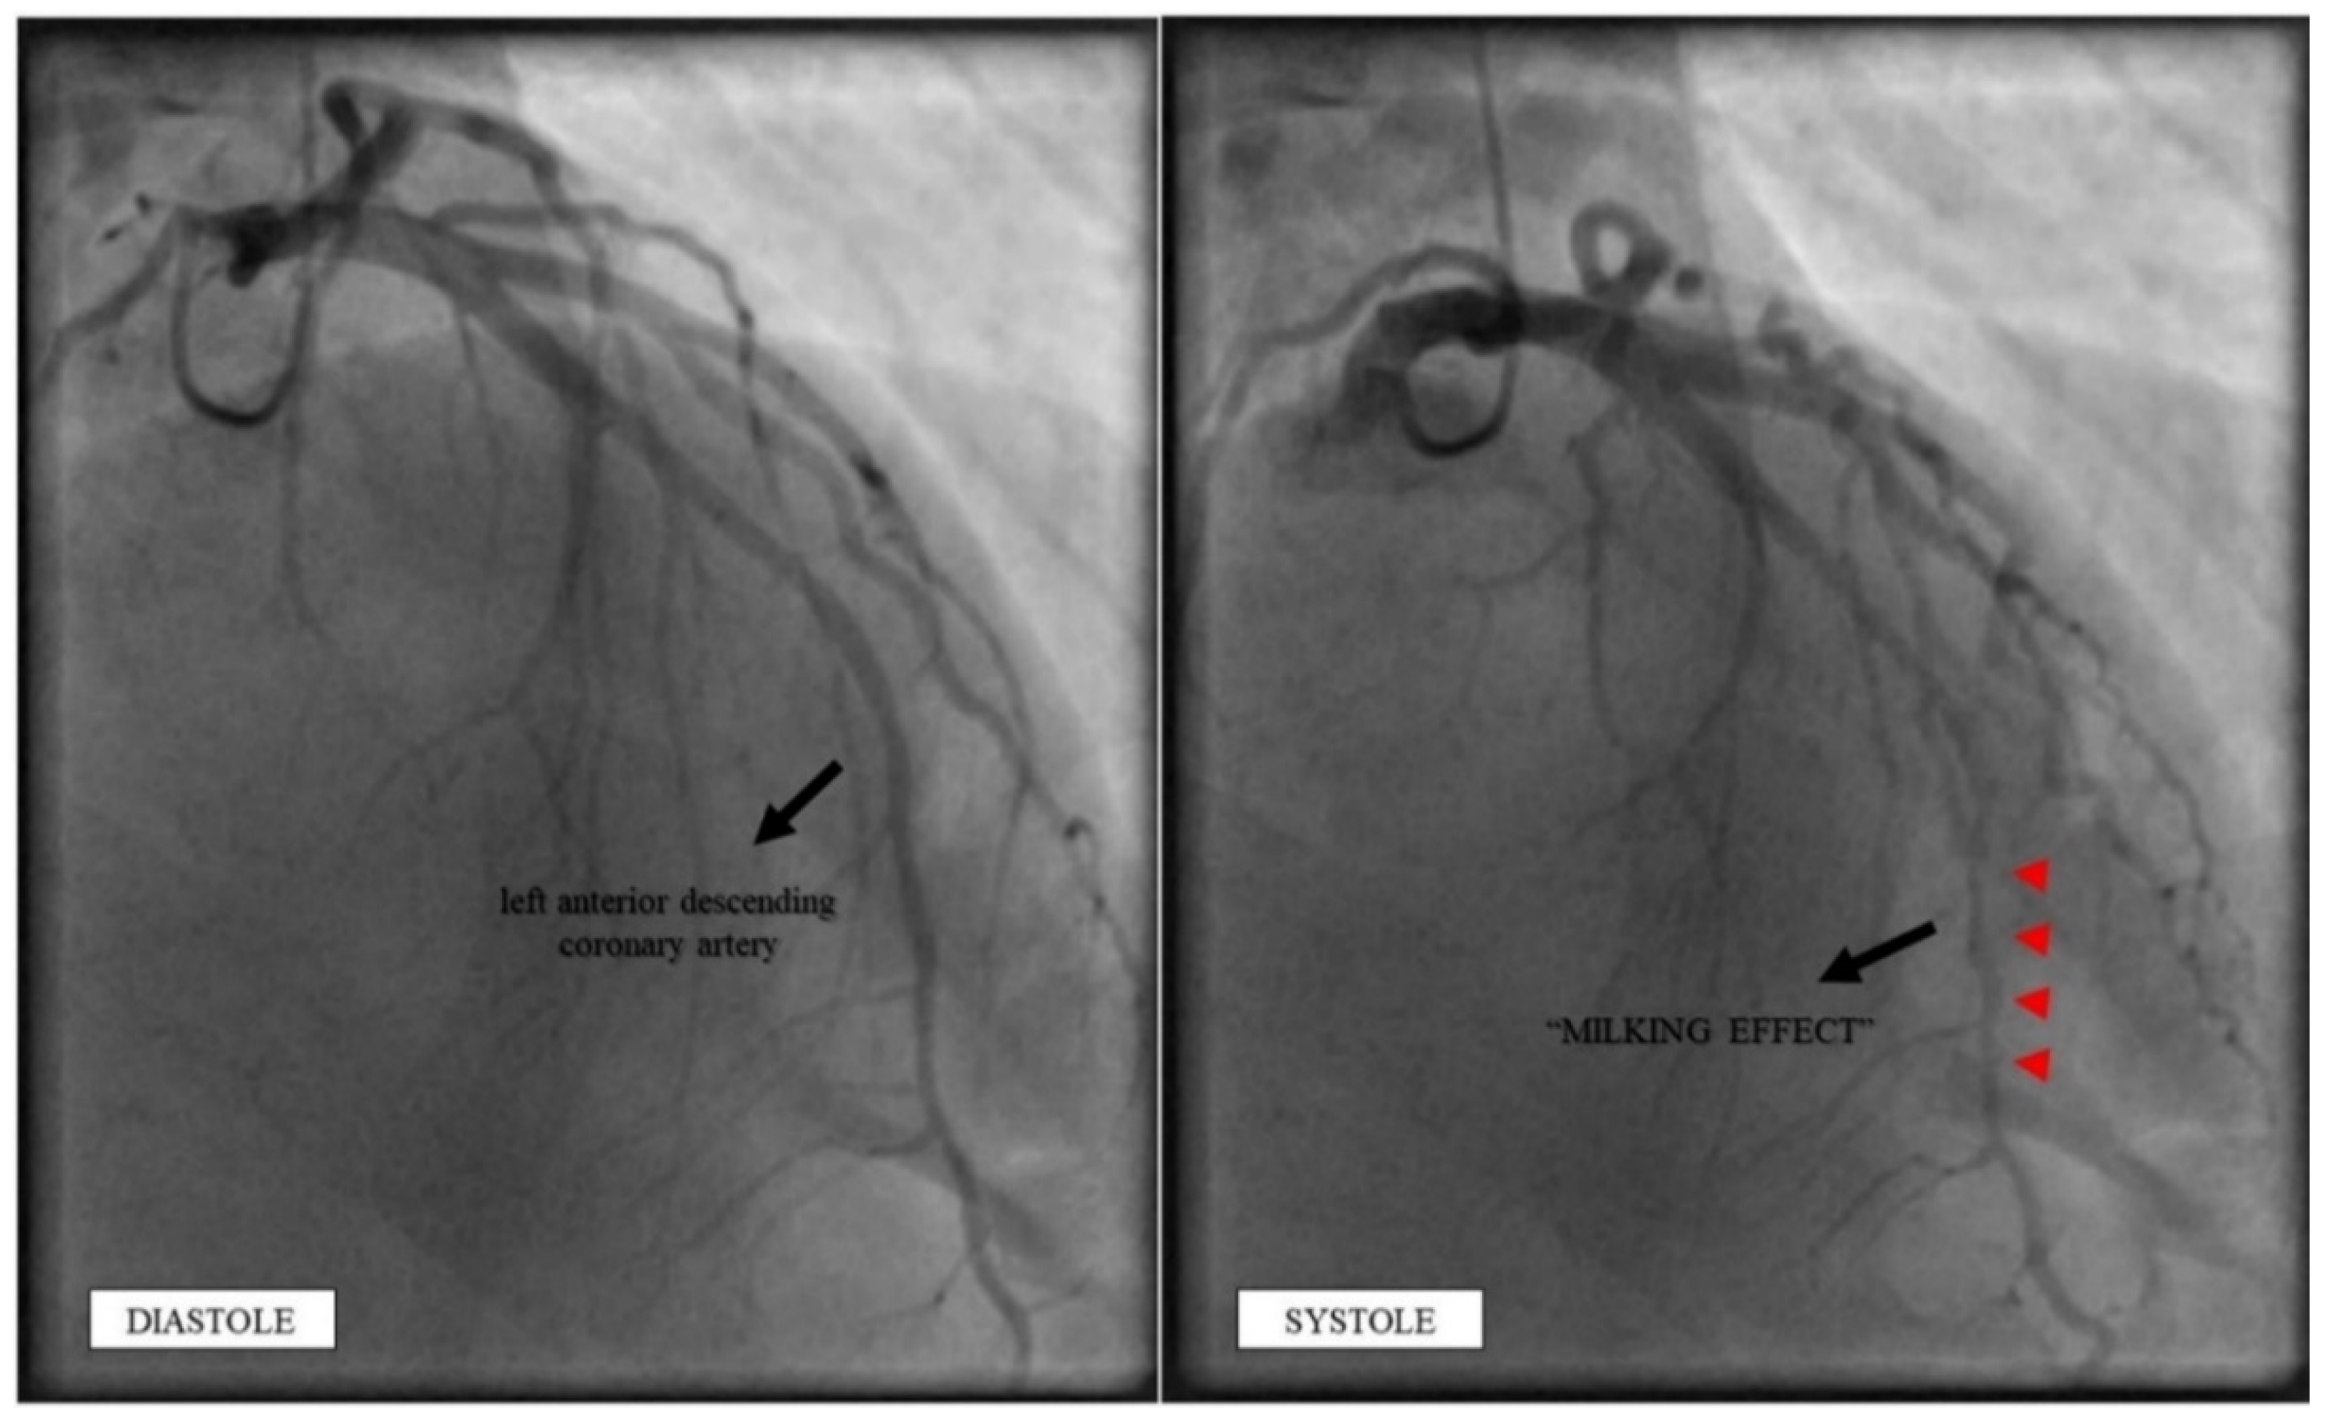

2.4. Investigations